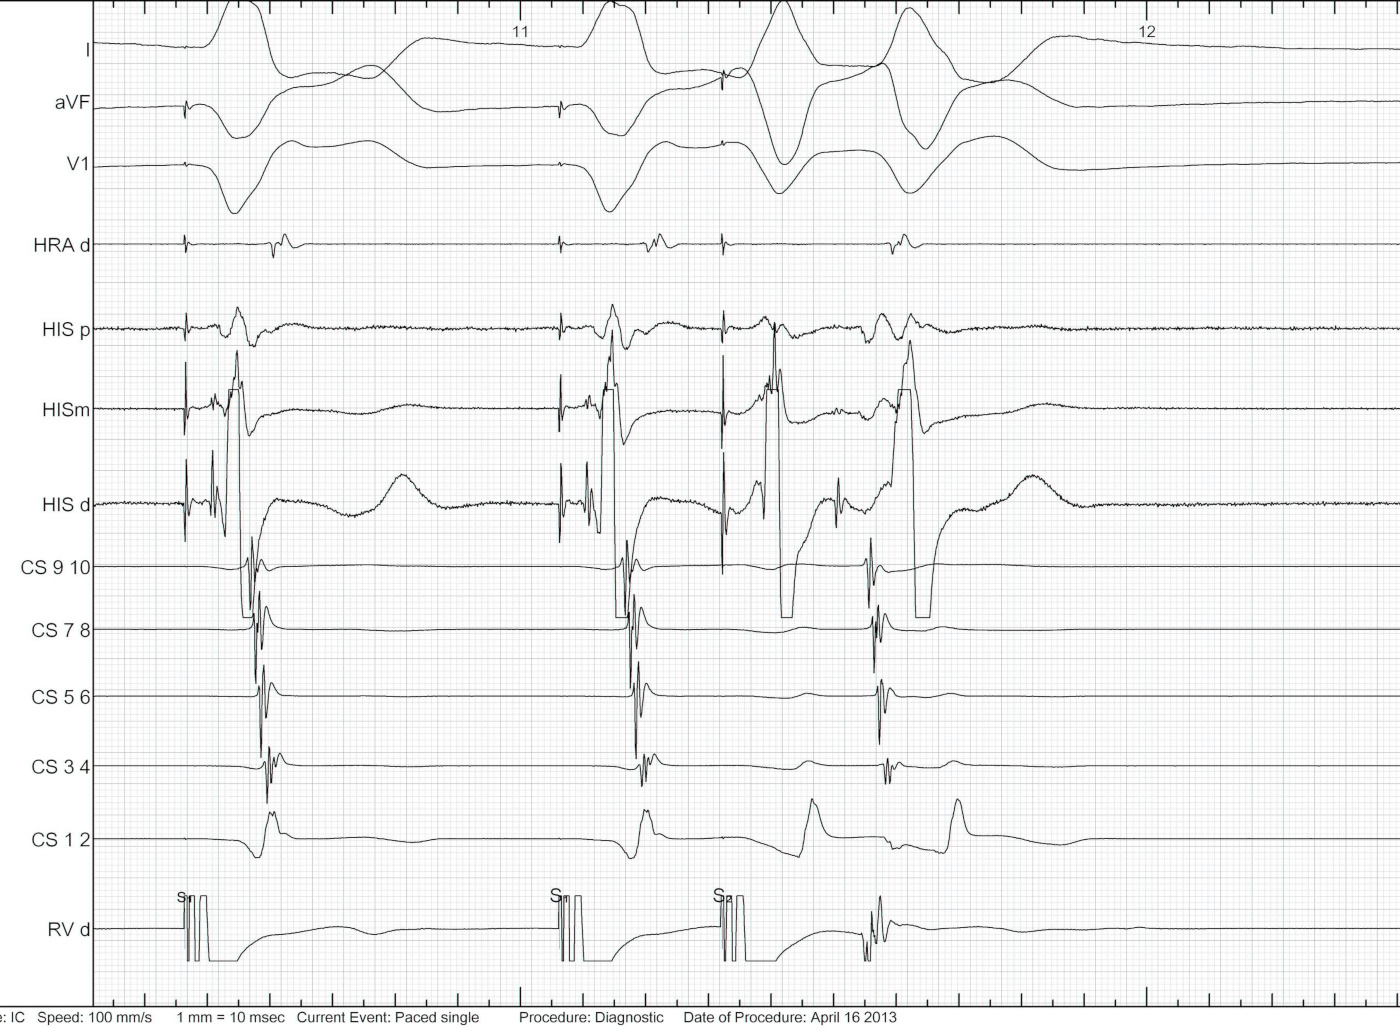

Parahisian pacing

parahisian_explanation.jpg

Parahisian

parahisian.jpg

parahisian_latha_2013-12.jpg